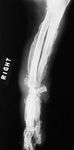

In a retrospective study of 210 dogs with primary lung tumors, paraneoplastic syndromes were observed, but their frequency was low (< 6%): Six dogs had radiographic signs of hypertrophic osteopathy (2.9%) (Figure 10), two dogs were hypercalcemic, two dogs had a fever, and two dogs had tumor-induced secretion of adrenocorticotropic hormone (ACTH).4 From other investigations, the development of hypertrophic osteopathy in dogs with primary lung tumors has been reported to range from 4% to 17%.2,12 Overt lameness and pain in dogs with primary lung tumors may not always indicate hypertrophic osteopathy, as skeletal metastasis could also cause similar clinical signs of pain and discomfort. Other less frequent hematologic paraneoplastic syndromes associated with primary lung tumors in dogs include absolute erythrocytosis and leukocytosis.43,44

10. A lateral forelimb radiograph of a geriatric dog presented for evaluation of severe lameness and pain. Note the extreme periosteal proliferation consistent with hypertrophic osteopathy. The dog had a primary pulmonary carcinoma. (Photograph courtesy of Dr. Laura Garrett.)